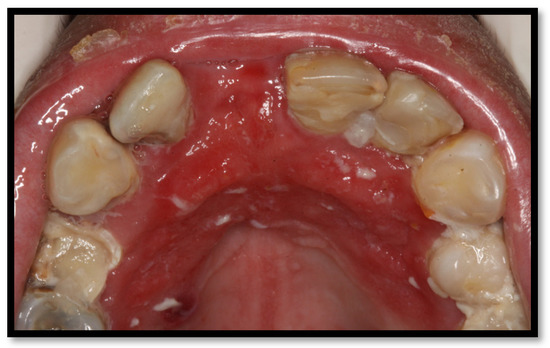

3.3. Necrotizing Gingivitis (NG)

3.4. Necrotizing Periodontitis (NP)